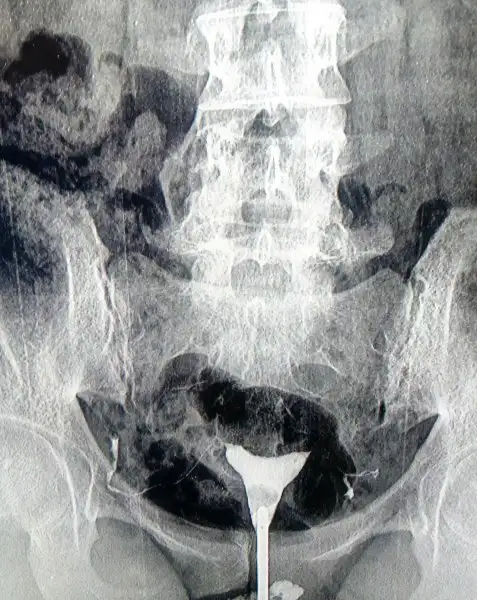

5 Dk sürdü ve ağrı olmadı. doktora dedim hiç ağrı olmadı çok hafif bi ağrı oldu. geri fışkırdı dedi. niye dedim rahim ağzı genişliğinden dedi. sonucu yarın gösterecem.

Rahim ağzı genişliği değil de darlığı olmasın canım o? Genelde rahim ağzı dar olanlarda rahim filmi pek sağlıklı sonuç vermiyor diye biliyorum.

• IMG_20161219_171526.webp

IMG_20161219_171526.webp

39,2 KB · Görüntüleme: 38

Genişliği dedi. hiç beğenmedim doktoru. kendi doktorum değildi onun için hemen olsun bitsin der gibi davrandı bir garip oblomov bir garip oblomov

kendi doktorun inşallah iyi şeyler söyler canım olmadı size de çektirmek istiyorum dersin memnun kalmazsa çekilmiş olandan.. gerçi 2 tane çekerler mi ya da sen tekrar ettirmek ister misin orasını bilmiyorum

Burda değil başka yerde çekilirim isterse.